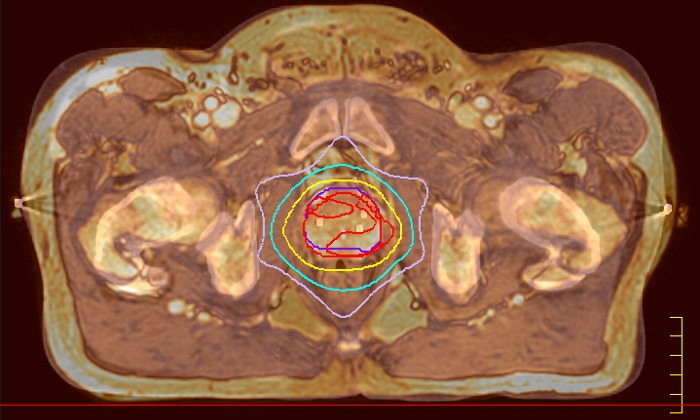

With its exceptional soft-tissue visualization capabilities and wide range of image contrasts, MRI has become a powerful tool to help more precisely define tumor boundaries. This is particularly important as it has been established that there is a high degree of uncertainty in target volume delineation, and it is even reported to represent the largest uncertainty in the entire radiotherapy process for most tumor sites**. Better visualization of the target area and nearby organs-at-risk is a key factor in enhancing target volume delineation. MRI’s expanding role also can be attributed to its functional imaging capabilities, which can inform both target characterization and treatment response.

With its superior soft tissue contrast compared to CT, MRI offers exquisite visualization of tumor boundaries and proximity to nearby critical structures.

Innovative strategies in MRI-only simulation have made it possible to derive CT-like electron density information from MR imaging data. This capability enables physicians to use MRI as the radiotherapy department’s primary imaging modality for specific applications to eliminate tedious and error-prone CT-MR registration and simplify workflows.

Our innovative MRCAT (MR for Calculating ATtenuation) clinical applications lets you plan radiation therapy using MRI as primary imaging modality. Within just one, fast MR exam, MRCAT provides both excellent soft-tissue contrast for target and OAR delineation and CT-like density information for dose calculations.